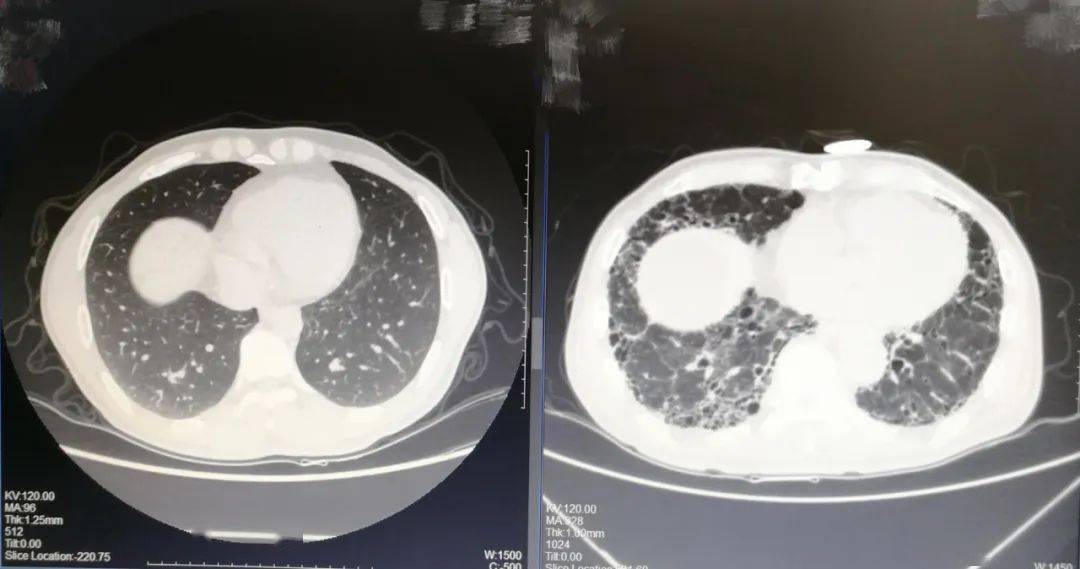

左为正常的肺部ct右为特发性肺纤维化的肺部ct考虑到特发性肺纤维化